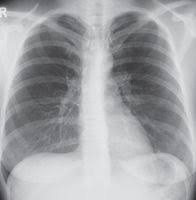

Lebensrettende Schockgerate Direkt Am Patienten Implantierbare Defibrillatoren Und Defibrillatorwesten Meduni Com Das Portal Fur Medizininteressierte

Lebensrettende Schockgerate Direkt Am Patienten Implantierbare Defibrillatoren Und Defibrillatorwesten Meduni Com Das Portal Fur Medizininteressierte from www.meduni.com